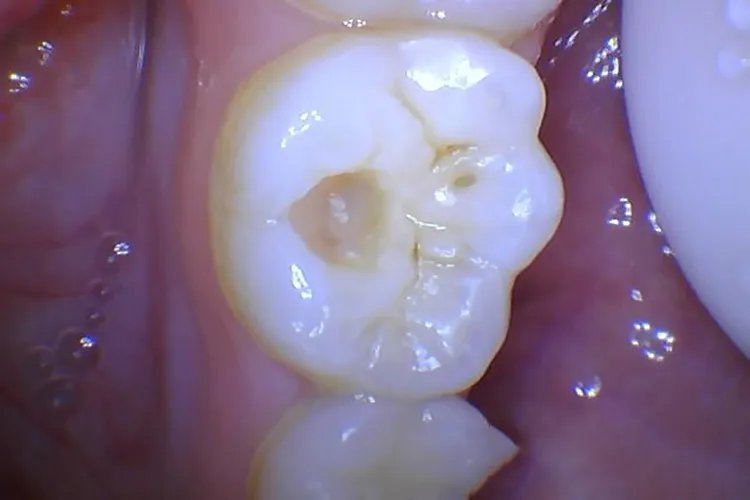

概述龋齿也称龋病,临床表现为牙釉质、牙本质和牙骨质颜色呈白垩色或黄褐色的改变,可形成龋洞,根据疾病发展可分为浅龋、中龋及深龋。龋病的发病因素复杂,主要与宿主、口腔微生物、饮食及时间因素有关。症状龋齿根据疾病发展可分为浅龋、中龋及深龋。浅龋龋坏局限于牙釉质,一般无自觉症状。初期平滑面表现为脱矿所致的白垩色斑块,以后因着色而呈黄褐色,窝沟处则呈浸墨状弥散,一般无明显龋洞,仅探诊时有粗糙感,后期可出现局限于釉质的浅洞。

中龋龋坏达牙本质浅层,对酸甜刺激敏感。龋损部位牙本质呈黄褐或深褐色,有龋洞形成,牙体缺损明显,病变牙本质质地较软。过冷过热饮食也能产生酸痛感觉,冷刺激尤为显著,但刺激去除后症状立即消失。

深龋龋坏达牙本质深层,对冷热刺激更为敏感。可见较深的龋洞,位于邻面的龋洞以及隐匿性龋洞,仅能从牙面看到一暗黑色区域,深龋洞口开放时,食物嵌人洞中会引起疼痛。刺激去除后,疼痛可立即消失。